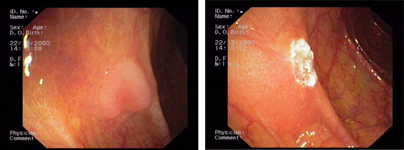

Endoscopic images:

imagen2

Kaposi's sarcoma in the stomach - Submucosal tumour of the oesophagus